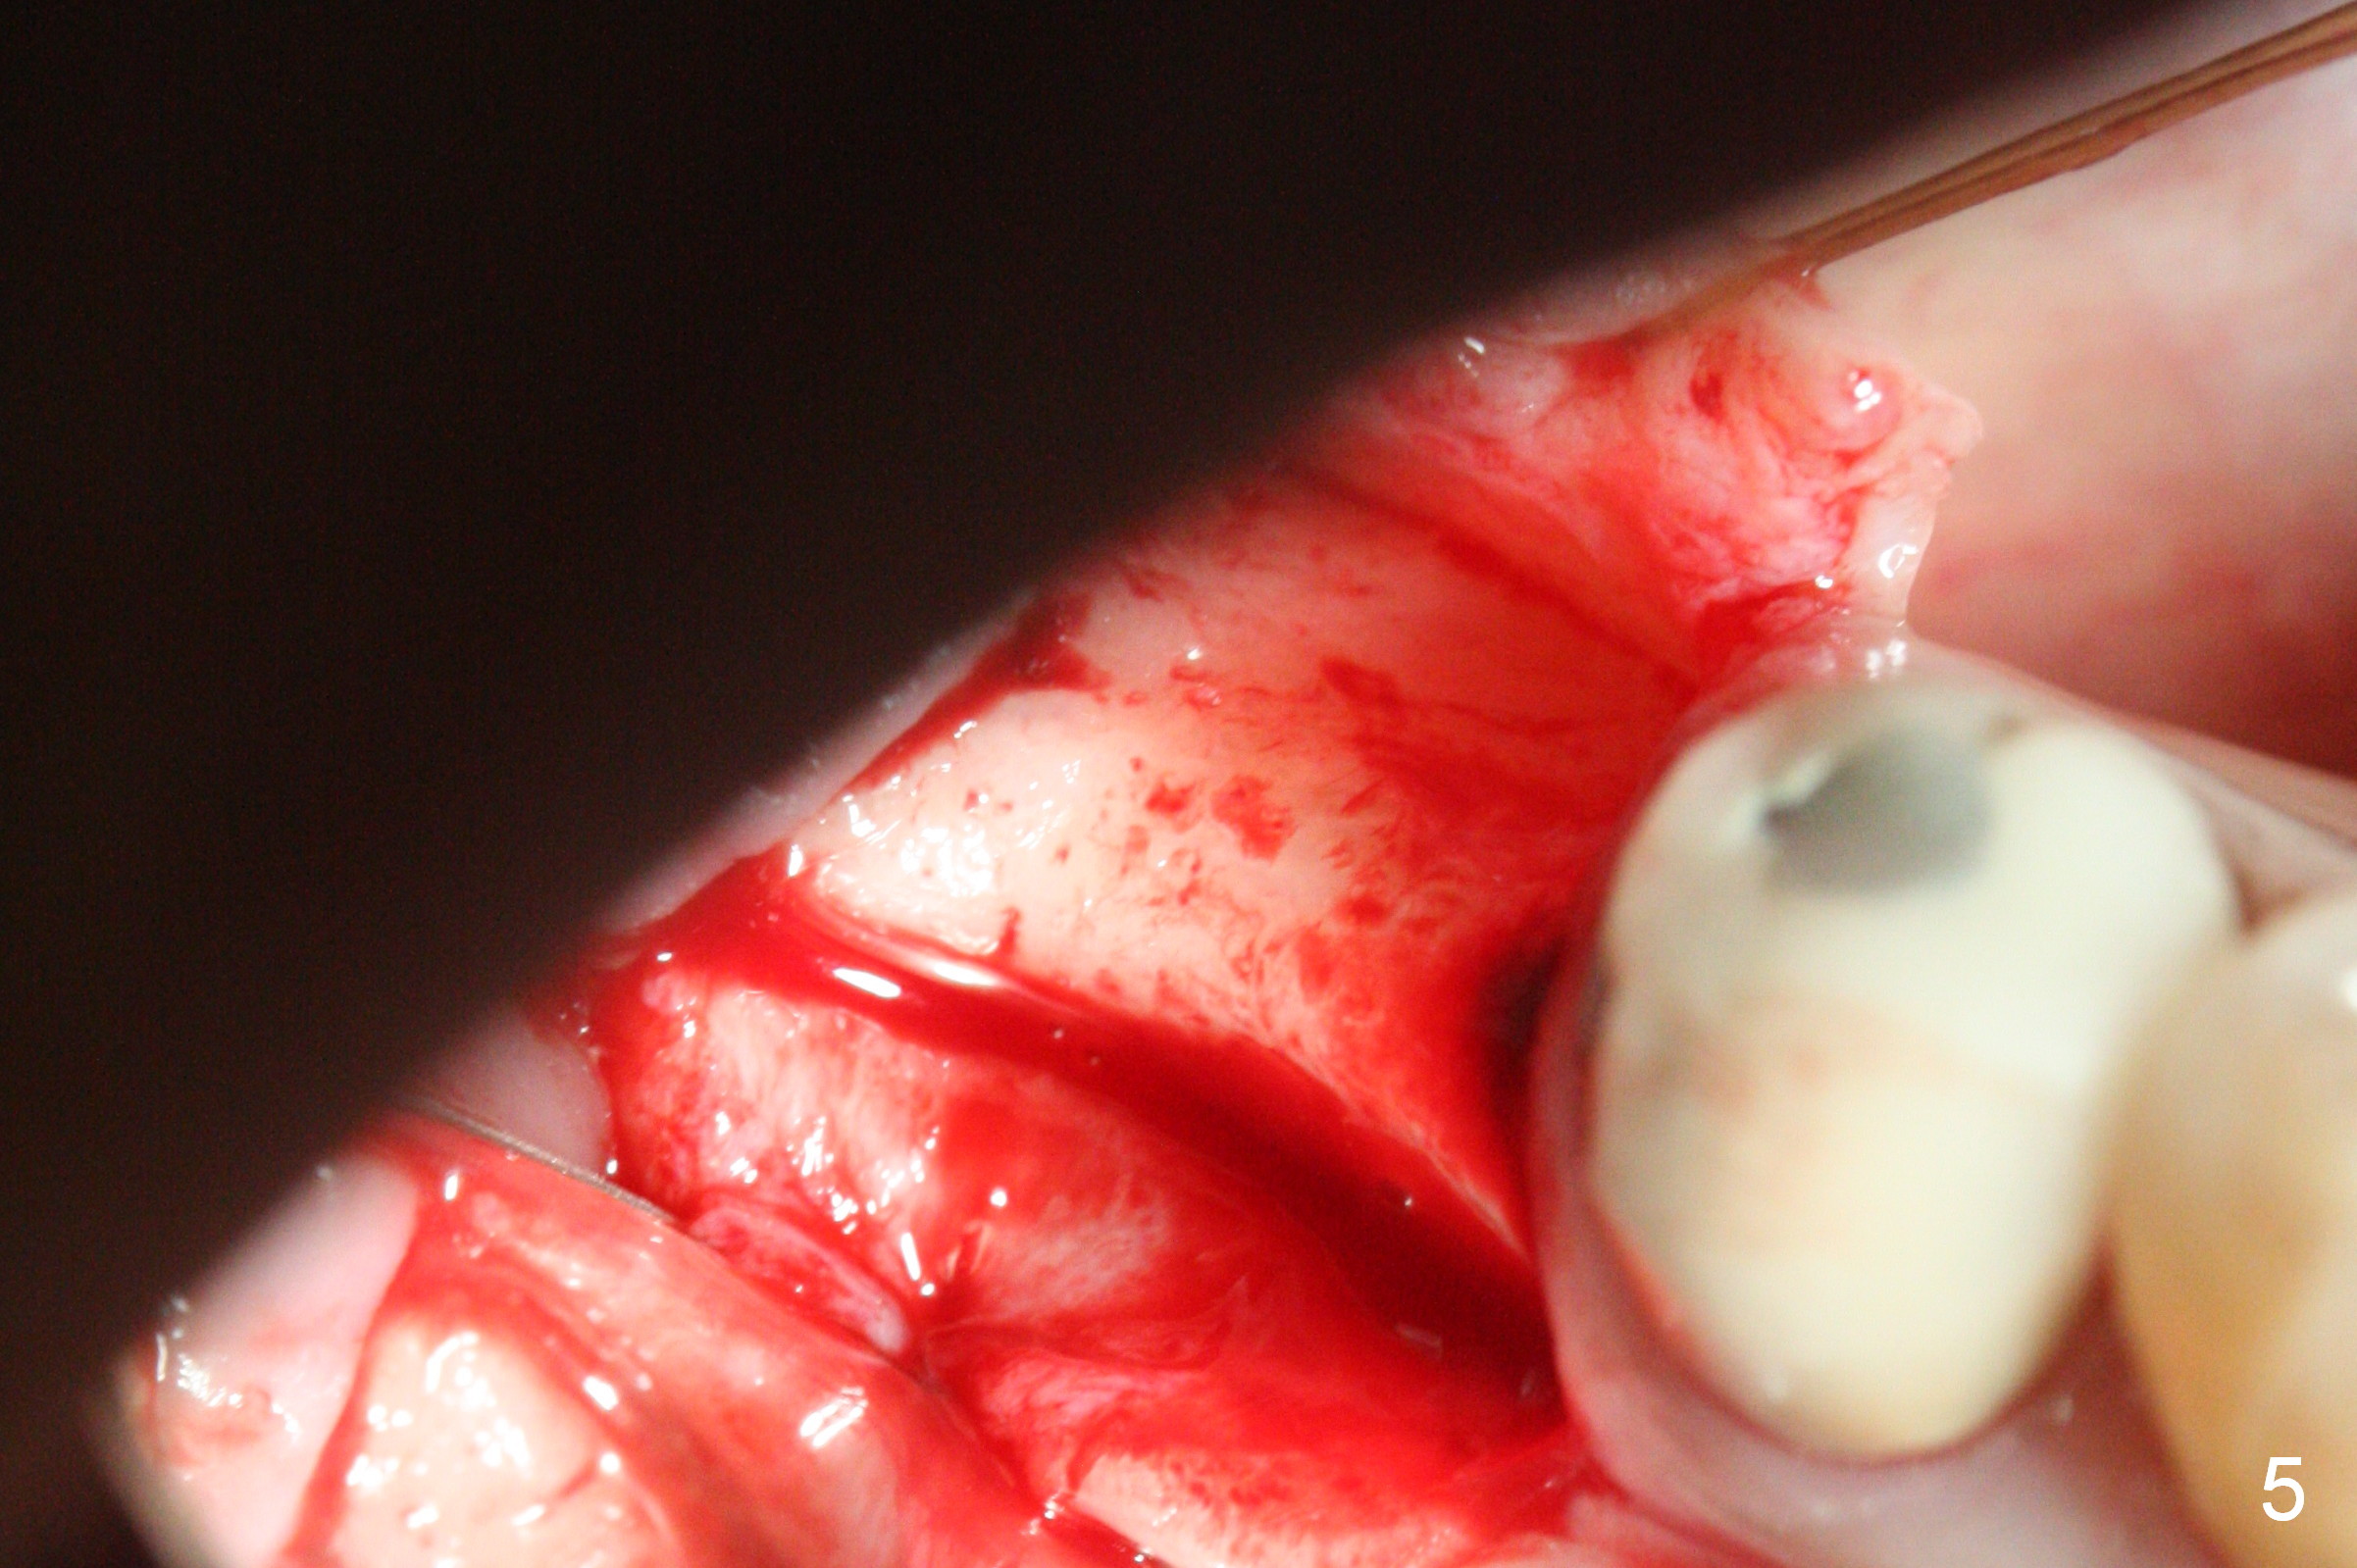

CBCT was taken (Fig.1,2 (P: pontic; S; submandibular fossa)) several months prior to #29 and 31 RCT and #31 porcelain chip (Fig.3). When the bridge is sectioned, the pointed ridge at #30 (Fig.1) is confirmed (Fig.4,5). After flattening the ridge until 6 mm buccolingually (Fig.6 arrowheads), osteotomy is initiated with 1.6 mm drill at 9 mm; there is 2.5 mm clearance from the superior border of the Inferior Alveolar Canal (red dashed line). A 4.5x9(1) mm Magicore is placed with 35 Ncm (insertion torque) after 4.3 mm Magic Drill; a 4.5 mm healing abutment (Fig.7 H). An error occurs because of using 1 mm cuff of the Magicore. Ideally 3 or 4 mm cuff should have been used because of reduction of the ridge by ~ 3 mm (Fig.2). The result of the error is failure of placing the implant at the desirable depth (<9 mm). The coronal threads are exposed and have to be covered by bone graft (autogenous bone and allograft (.5-1.5 mm) (Fig.8 *), followed by collagen dressing. Extra suturing is done to securely close the wound (Fig.9), followed by periodontal dressing (data not shown).